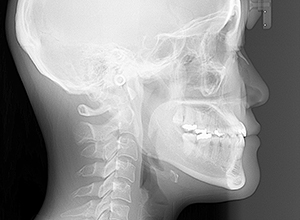

初診時

FP・IOP

X-Ray

X-Ray所見

セファロ所見 下顎頭はやや後方に位置しているが、下顎は大きく力強い形態をしており下顎角は平均的であるのに対して、中顔面部は奥行きがなく前後的には後方に位置づいており劣位であるため、下顔面高は低く垂直的にはShort face様骨格形態を呈していた。

パノラマ所見 上顎両側8が存在していた。下顎臼歯は近心傾斜が認められた。